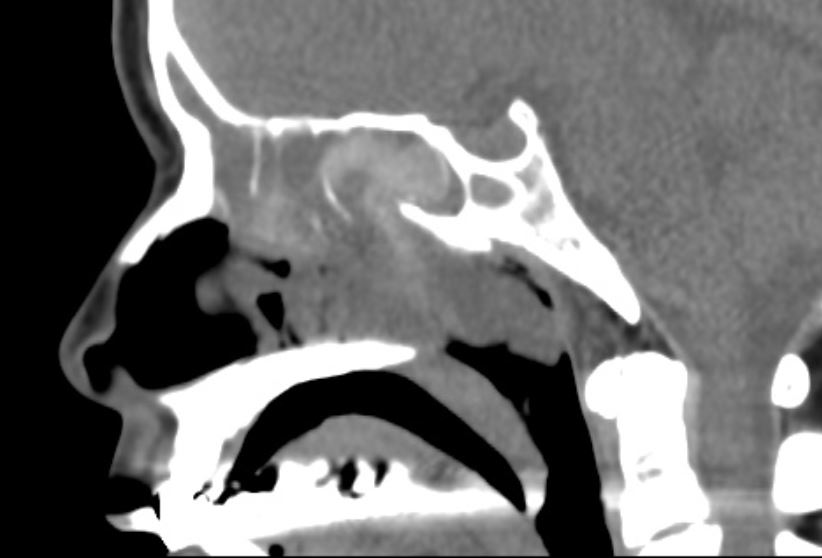

门诊鼻内镜检查提示:鼻窦炎伴鼻息肉。10年前曾在佛山第二人民医院行"鼻内镜鼻息肉切除+鼻中隔偏曲矫正手术"。但这次是明显的复发了,需要再次的手术治疗。

这次做了全麻鼻内镜鼻息肉切口鼻窦开放术,手术做的非常的顺利。但该手术术后需要进一步的治疗鼻炎,术后也对患者的鼻炎做了相应的治疗,再加上术后的治疗,只要鼻炎控制的好,一般复发的可能就会明显的减少。